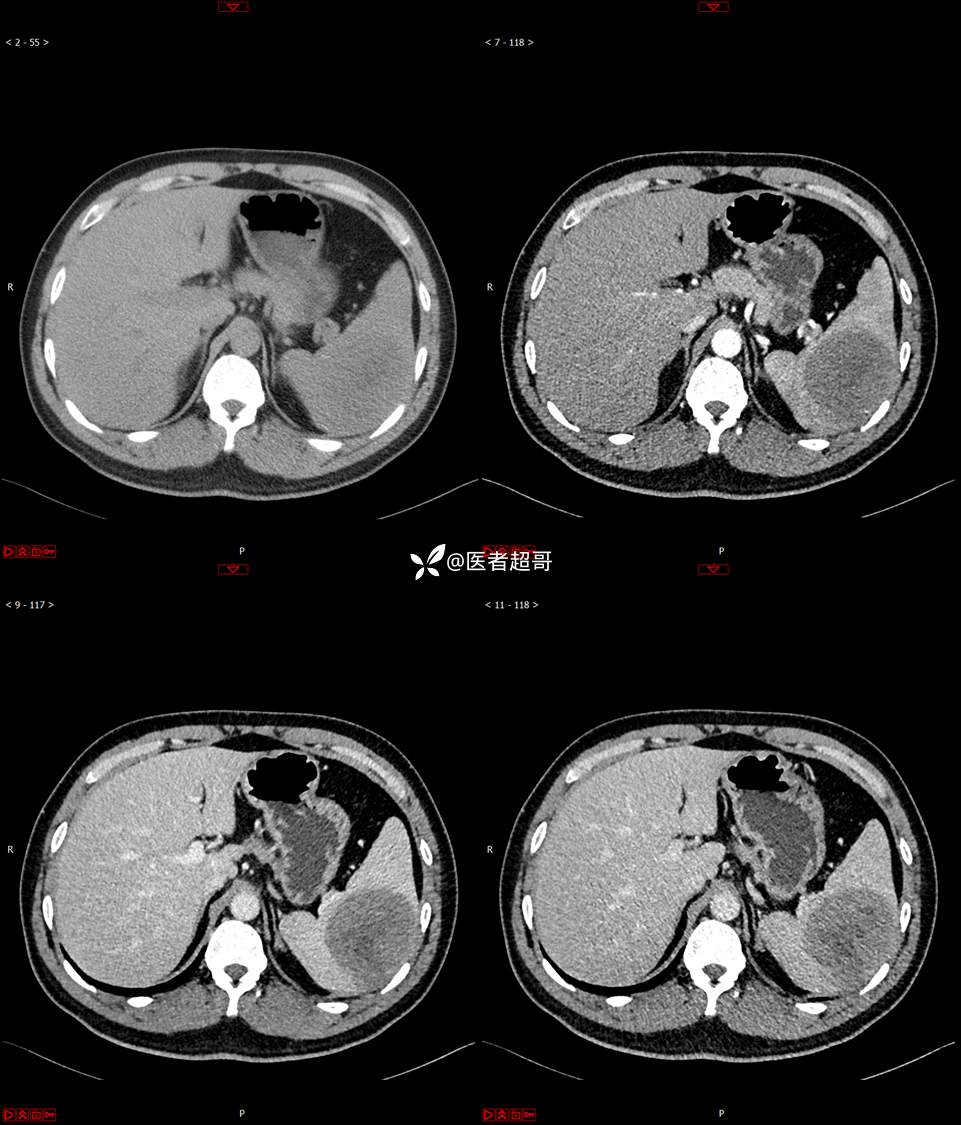

【影诊笔记738】脾脏低密度影,请诊断分析~~

男,33岁 0201215 01

主 诉:发现脾占位2月余。

现病史:患者2月余前体检行肝胆胰脾肾彩超提示脾占位性病变,未予特殊诊治,1天前于区人民医院行肝胆胰脾MR平扫提示脾脏占位性病变,左肾小囊肿,现患者无腹胀、腹泻,无恶心呕吐,无胸闷憋气等症状,今为求进一步治疗,患者来我院就诊,门诊以“脾占位性病变”收入院。患者自发病以来,一般情况可,神志清,精神可,饮食、二便正常,睡眠可,体重体力无明显改变。